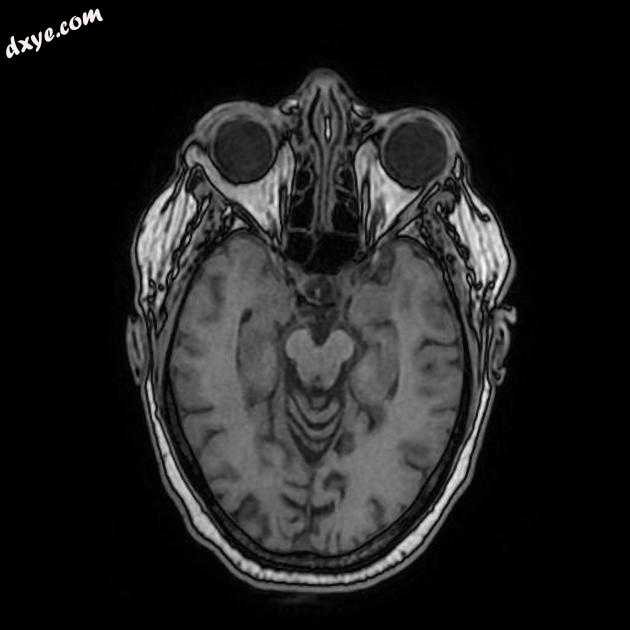

Axial T1

MRI 序列显示左侧大脑中动脉 (MCA) 区域分布中的弥散受限区域,在 FLAIR 序列上不可见。在 GE 序列上没有看到出血性转化。 MRA 3D-TOF 显示左侧大脑中动脉完全闭塞。

早期超急性大脑中动脉 (MCA) 区域梗死的 MRI 特征。